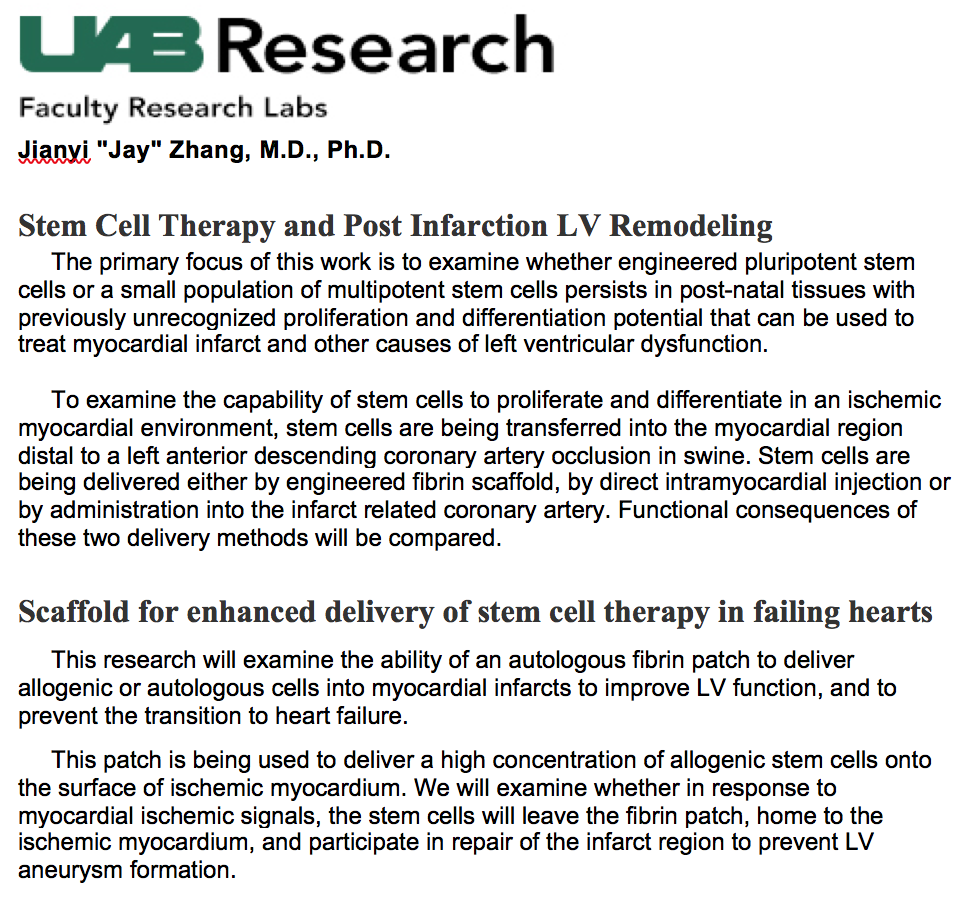

Patching the Heart - Cardiac Repair From Within and Outside - 2013 review article - Circulation - Zhang et al

Engineering Tissue for Cardiac Repair - Zhang - UAB

Cardiac Repair of Myocardial Infarction Using Human Stem Cells - Cell Stem Cell - 2014

A Large Scale Investigation of Hypoxia-Preconditioned Allogeneic Mesenchymal Stem Cells for Myocardial Repair in Nonhuman Primates - Circulation Research - 2016

UAB Researchers Take on 5 Key Areas of Cardiovascular Disease - Medscape - 2016

Cardiac Tissue Chips (CTCs) for Modelling Cardiovascular Disease - Transactions on Biomedical Engineering - 2019